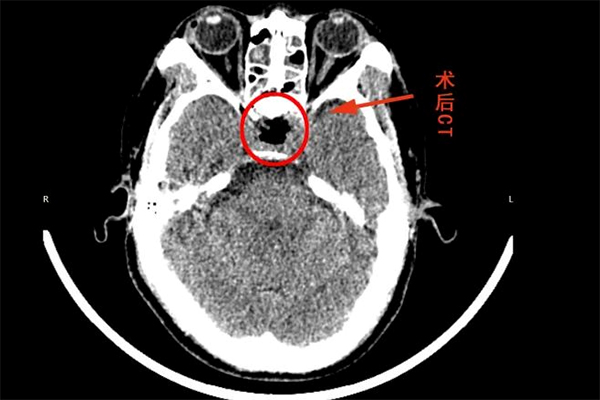

謝宏剛主任針對(duì)患者病情進(jìn)行了詳細(xì)分析,認(rèn)為垂體腫瘤位置深,臨近視神經(jīng)、海綿竇等重要結(jié)構(gòu),手術(shù)風(fēng)險(xiǎn)和難度比較大,預(yù)先與團(tuán)隊(duì)分析了術(shù)中可能存在的風(fēng)險(xiǎn)及處理方案,在做好了充分的準(zhǔn)備后,歷時(shí)4小時(shí),成功為患者進(jìn)行手術(shù),術(shù)后復(fù)查CT手術(shù)效果滿意,不日即可出院。

▲ 術(shù)后頭部CT